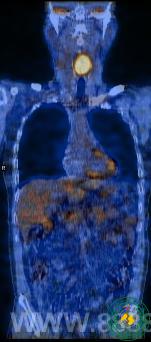

PET/CT作为生物分子影像,一问世就给医疗影像诊断世界带来了革新,特别在肿瘤疾病方面获得了重大价值,其价值体现在临床医生对其充分的认识和应用。我院PET/CT投入近一年来,诊断多起疑难病例,为临床提供了重要诊疗信息,现就部分病例汇报,以供交流:病例1为颈部淋巴结肿大患者,外院病检为淋巴结转移鳞癌,外院三甲医院头颈部CT未见原发灶,胸片未见异常,我院PET/CT发现喉咽部高葡萄糖代谢灶,诊断恶性病变。回顾看外院CT片,发现喉咽后壁已明显增厚,只是增强不明显而漏诊,后我院MRI进一步显示为恶性肿瘤。病例2为发现脑部转移灶,常规胸片及其他部位未见原发灶,PET/CT见右肺门局限性高葡萄糖代谢灶,临近气管受压,诊断肺Ca,进一步诊断性CT印证了PET/CT的发现,肺门结构复杂,肿块不大时易漏诊。病例3为淋巴瘤放化疗多个次的患者,患者无不适症状,颈胸部检查正常,PET/CT意外发现腹主动脉旁淋巴结异常高代谢,诊断淋巴瘤(未痊愈),为临床进一步治疗提供依据。

病例3:淋巴瘤放化疗几个疗程后,PET/CT发现腹部残留病灶